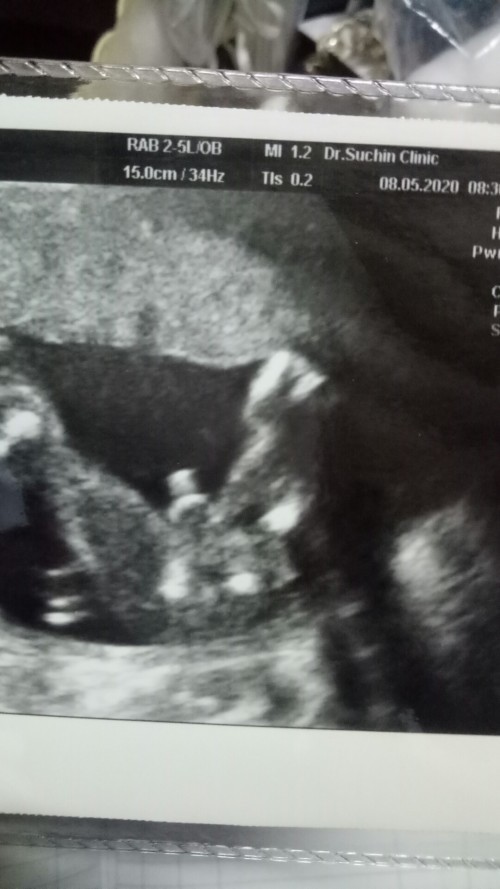

6เดือนนิดๆค่ะ

Post reply image